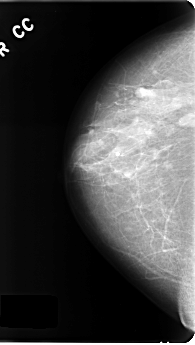

C_0177_1.RIGHT_CC

RIGHT_CC LINES 4824 PIXELS_PER_LINE 2728 BITS_PER_PIXEL 12 RESOLUTION 50 NON_OVERLAY